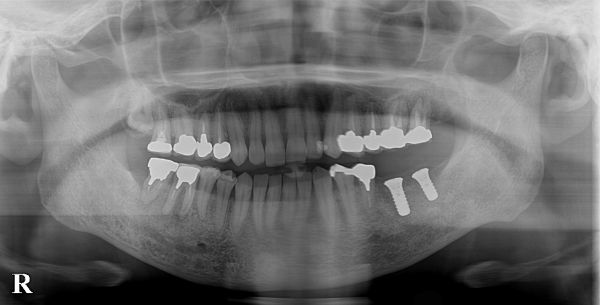

こちらが被せ物が入った後のレントゲン写真になります。

治療後患者様はインプラント治療に大変満足されております。

治療によって奥歯がしっかり入り、違和感なくしっかりお食事ができているとのことです。